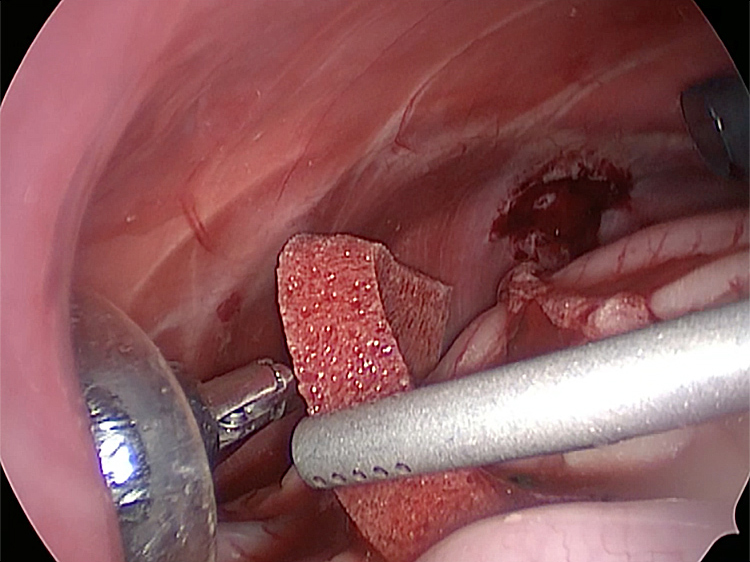

お腹にトロッカーを4本挿入し、そこから鉗子とカメラを入れて胆嚢を肝臓から剥がしていきます。 カメラで拡大しながら見ることができるので開腹手術よりも視野が確保できます。

手術の様子

胆嚢の周囲の脂肪や膵臓、十二指腸が激しく癒着し剥離が困難な状態でした。胆嚢は全く確認することができませんでした。

少しずつ癒着を剥がして胆嚢が確認できるようになってきました。 こんなに癒着していることはあまりないので過去に膵炎や胆嚢炎を起こし苦しい時期があったことが推測されました。 それにしてもなかなか胆嚢はでてきませんでした。

丁寧に丁寧に出血をコントロールしながら少しずつ手術をすすめていきます。

癒着(矢印)がひどく胆嚢を確認することができませんでした。 このように癒着しているときはギリギリで剥がすとひどく出血をおこすことがあるので無理にはがそうとしないで、脂肪の血管に注意しながら脂肪ごと剥がしていきます。

胆嚢を少しずつ丁寧に肝臓から剥がしています。